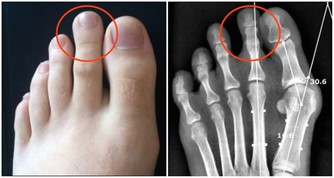

黃慧娟中醫師表示,馬齒莧屬性甘、酸、寒,具有清熱解毒、消炎止痛和活血消腫的作用,可用於治療泌尿道感染、便秘、青春痘、癰瘡腫毒、濕疹和女性白帶。另外,馬齒莧對於熱性腹瀉,例如細菌感染引發的拉肚子,也有不錯的改善效果;熱性腹瀉的症狀為肛門熱脹痛、排泄物呈稀黃狀。

中醫認為馬齒莧屬性甘、酸、寒,具有清熱解毒、消炎止痛和活血消腫的作用。

馬齒莧多生長於鄉下田間、路旁和山野間,不管春夏秋冬、雨季和乾季,一年四季都生長力十足,但仍以春季較為盛產,食用部位為葉部和嫩莖,炒食、煮湯或做成涼拌菜都很適合。然而,黃慧娟中醫師特別提醒,馬齒莧性質較冷寒,虛冷體質或腸胃功能不佳的人,不宜食用。